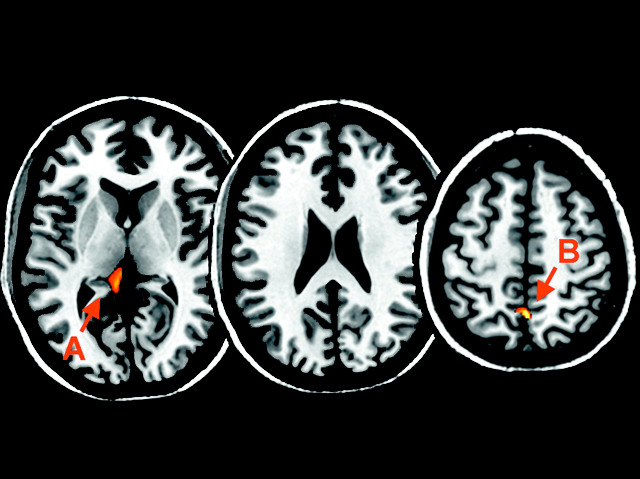

During a stroke, reduced blood supply to part of the brain often results in paralysis on one side of the body. If the mind ‘learns’ that a limb cannot move, paralysis then becomes a habit, even when connections from brain to limb are restored. Stroke recovery is improved with mirror box therapy, where an illusion of the paralysed limb moving is produced from the mirror-image of movement in the matching, healthy limb. How this works is not clear but scientists have started to unravel the regions of the brain involved using functional Magnetic Resonance Imaging (fMRI), which employs magnetic fields to observe changes in brain activity. Two regions, labelled A and B in the image, are activated. Both are important for self-awareness and memory, but not for muscle movement. Could mirror box therapy be helping the brain to ‘unlearn’ paralysis by making it conscious that a limb can move?